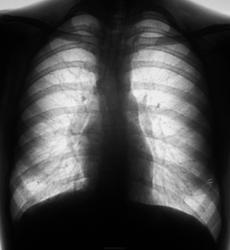

Результат выдали. Первая "флюшка" за апрель 2011 год, вторая - март 2012 год.

Резко усилен лёгочный рисунок в верхних, средних и нижних полях с обеих сторон, обогащён за счёт очаговоподобных теней без чётких контуров. Корни лёгких расширены, малоструктурны. Дуги соr нечёткие за счёт суперпозиции изменённого лёгочного рисунка. Анамнез.

Флюшка делалась, когда пациентка была здоровенькая в ортоположении.